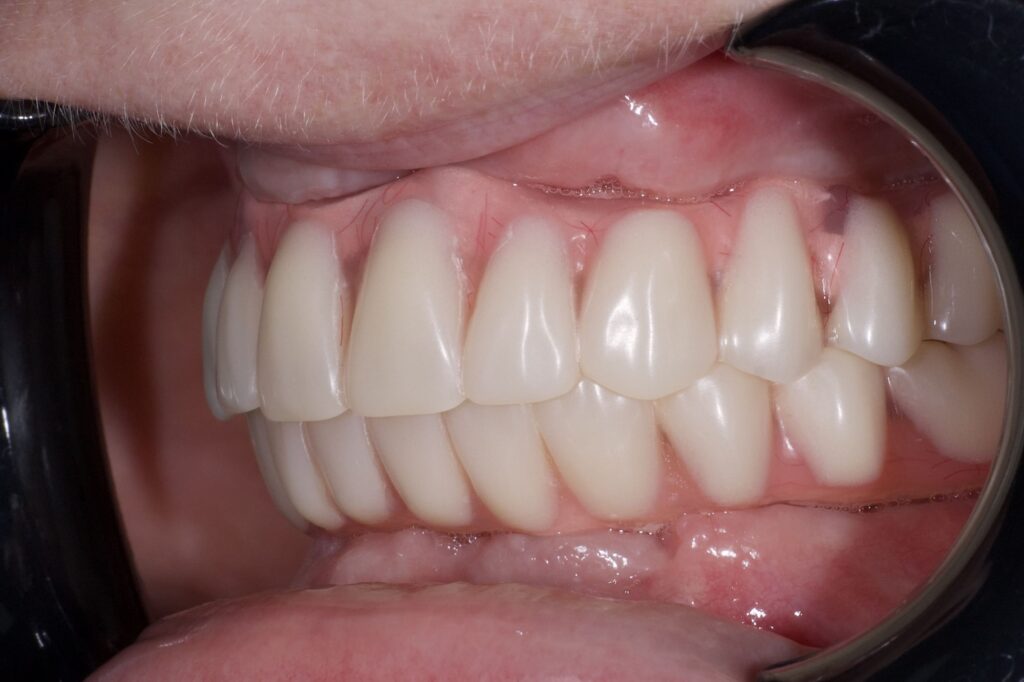

Пациент обратился к нам с целью перепротезирования на постоянные протезы (комплексная имплантация по системе All-on-6 на обе челюсти была проведена в 2024г. специалистами нашей клиники).

По прошествию года было изготовлено 2 постоянных циркониевых протеза на титановой балке.

результат протезирования